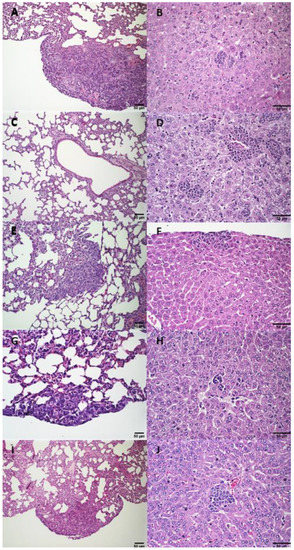

3.2.4. Histological Analysis

3.3.2. Histological Analysis